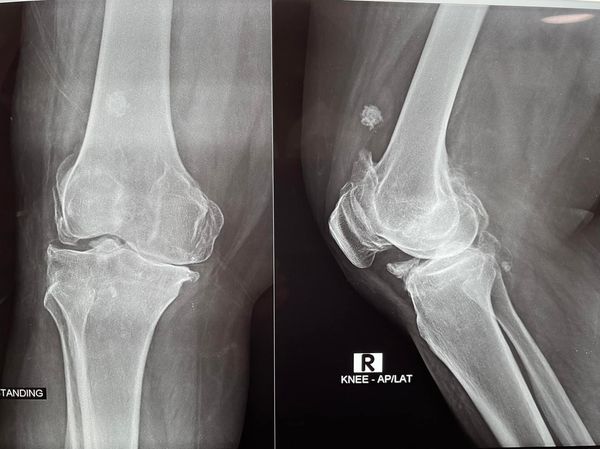

68 year old man ACL (anterior cruciate ligament) reconstruction of Knee

There used to be a common consensus that ACL reconstruction of knee should not be done in old age, this idea has now largely been debunked with statistical evidence. this 68 year old man with a traumatic anterior cruciate ligament tear had intact lateral and medial meniscus and quite normal cartilage in the weight bearing […]